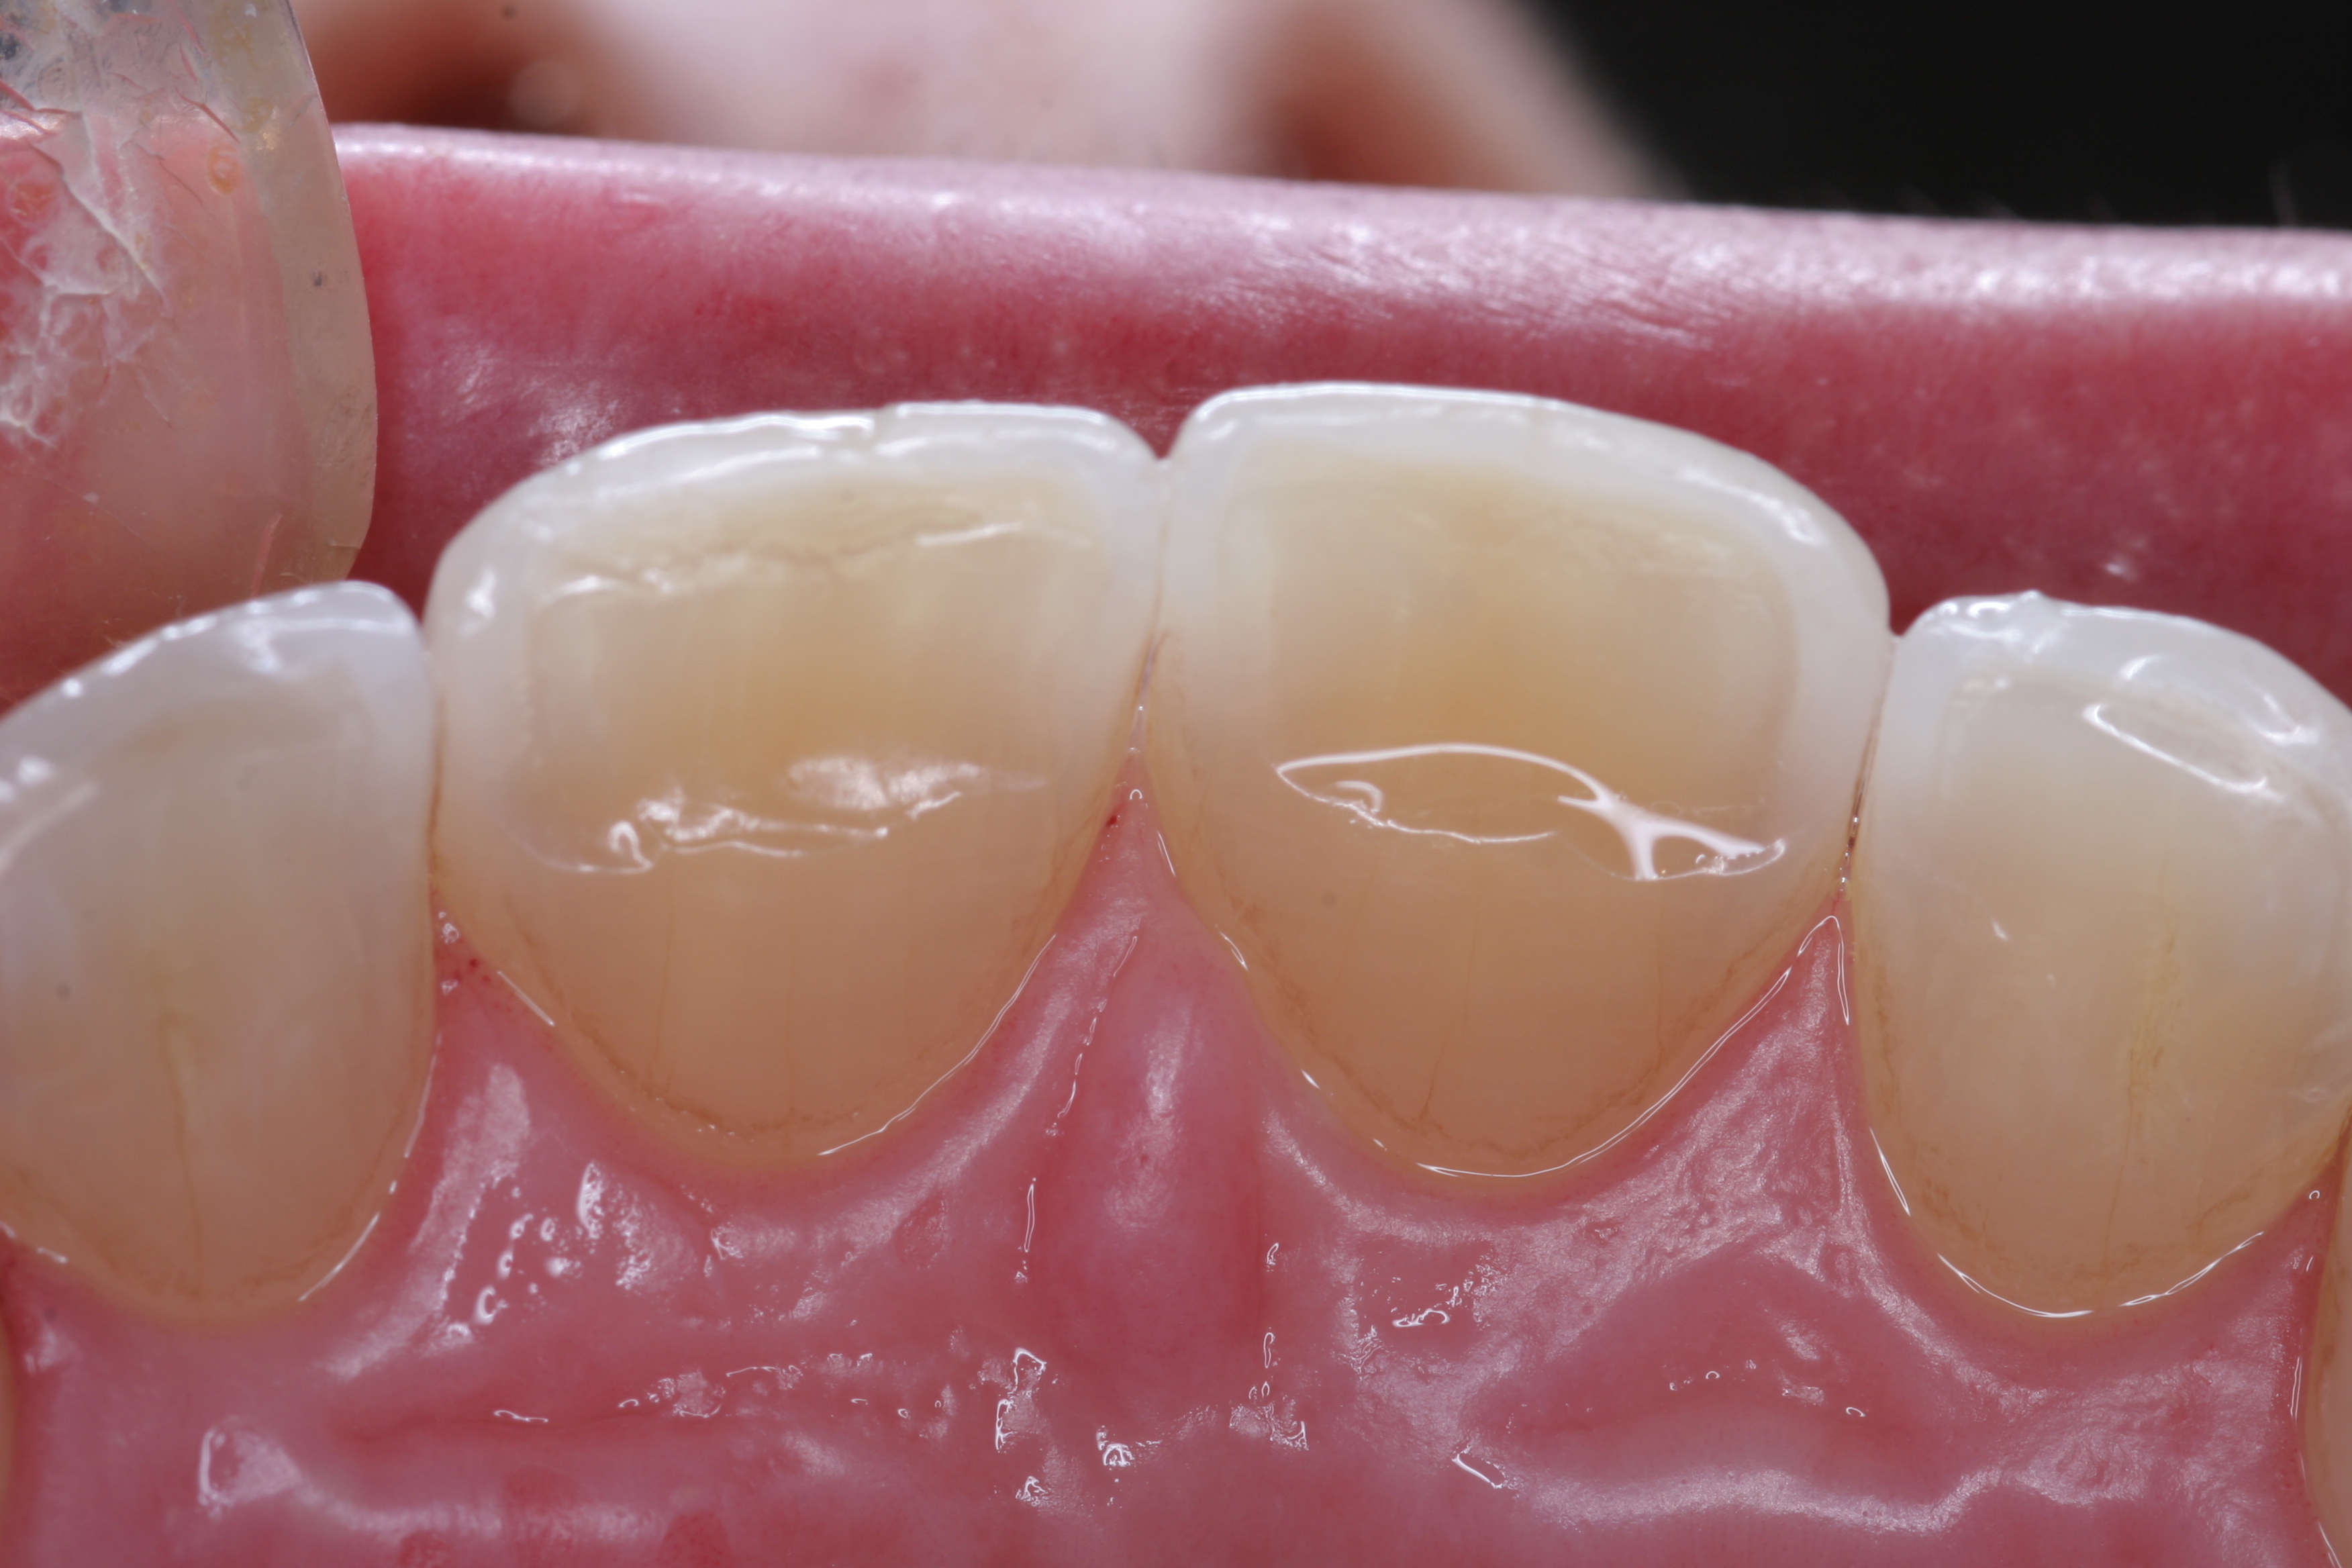

(11.) A patient presented with advanced generalized wear of her anterior teeth, and was displeased with their overall appearance because of their color and wear.

Figure 11

(12.) A patient presented with advanced generalized wear of her anterior teeth, and was displeased with their overall appearance because of their color and wear.

Figure 12

A patient presented with advanced generalized wear of her anterior teeth (Figure 10 and Figure 11). She was displeased with their overall appearance because of their color and wear (Figure 12). A complete examination was performed, revealing instability in her temporomandibular lateral poles bilaterally, sore muscles of mastication, advanced wear, a CR/MIP discrepancy, and loss of her anterior guidance due to the wear. Although the topic is beyond the scope of this article, the patient was also screened for possible sleep apnea. This included an evaluation of the Mallampati score, previous sleep therapy evaluation or treatment, snoring history, an evaluation of her neck size, her weight status, and the presence of the tonsils and their size. In every case, if this clinician suspects airway obstruction to be playing a role in tooth wear issues, the patient is referred to a sleep physician. The patient in this case displayed few apnea risk factors, and the patient’s anterior wear facets fit together like a “lock and key” pattern seen in parafunctional activity. Splint therapy was initiated to stabilize the joints and muscles. A repeatable CR position was verified through load testing. At this point diagnostic models, photographs, a CR bite record, and a facebow were taken and recorded.